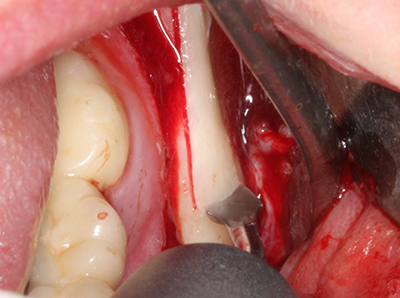

When surgical procedures are performed on bone in the immediate vicinity of sensitive structures such as blood vessels or nerves, rotary instruments pose a significant risk of iatrogenic injury. Piezoelectric devices can be helpful for preparation of bone covers and removal of hard tissue close to nerves, particularly for exposure of nerves after iatrogenic injury but also during nerve lateralization for resective and reconstructive procedures or implant placement (Fig. 17-20). Light contact between the piezotip and the nerve does not generally result in damage but proceeding incautiously with saw-like motions or attachments where a residual bone substrate remains may cause temporary or even permanent nerve damage. However, the risk of damage is considered to be substantially lower than when using saws or milling instruments (Pereira, Gealh et al. 2014).

Fig. 18: Preparation of a cortical cover with the piezo bone saw (Piezomed, W&H).

Fig. 19: Surgical site after neurolysis and removal of osteoma.

Fig. 20: The removed bone cover is re-adapted and fixed with an osteosynthesis screw (KLS Martin, Tuttlingen).